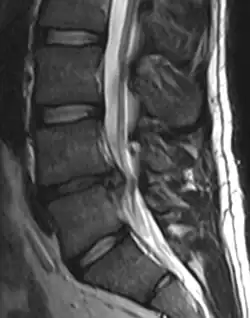

• Magnetic resonance imaging is the gold standard study for confirming a suspected LDH. With a diagnostic accuracy of 97%, it is the most sensitive study to visualize a herniated disc due to its significant ability in soft tissue visualization. MRI also has higher inter-observer reliability than other imaging modalities. It suggests disc herniation when it shows an increased T2-weighted signal at the posterior 10% of the disc. Degenerative disc diseases have shown a correlation with Modic type 1 changes. When evaluating for postoperative lumbar radiculopathies, the recommendation is that the MRI is performed with contrast unless otherwise contraindicated. MRI is more effective than CT in distinguishing inflammatory, malignant, or inflammatory etiologies of LDH. It is indicated relatively early in the course of evaluation (<8 weeks) when the patient presents with relative indications like significant pain, neurological motor deficits, and cauda equina syndrome. Diffusion tensor imaging is a type of MRI sequence used for detecting microstructural changes in the nerve root. It may be beneficial in understanding the changes that occur after herniated lumbar disc compresses a nerve root, and might help in differentiating the patients that need surgical intervention. In patients with a high suspicion of radiculopathy due to lumbar disc herniation, yet the MRI is equivocal or negative, nerve conduction studies are indicated.[44] T2-weighted images allow for clear visualization of protruded disc material in the spinal canal.